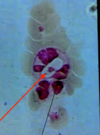

Leishmania sp.: Amastigotes

Divided & intracellular - Only in macrophages